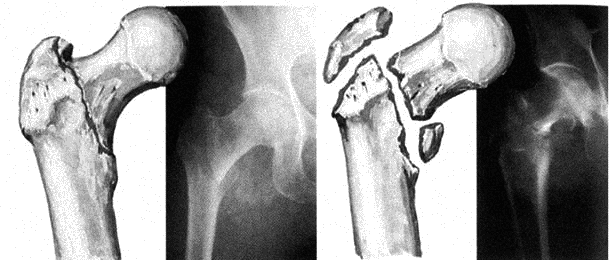

Для оценки состояния кости используется рентгенография, которой располагает практически каждое лечебное учреждение. Однако рентгенологически можно оценить плотность костной ткани только при потере более 30 % костной массы, когда на рентгеновских снимках появляется крупнопетлистый рисунок кости, истончение кортикального слоя и подчеркнутость его краев (рис. 6.4).

Рис. 6.4. Диагностика остеопороза

Деформация тел позвонков является результатом микропереломов трабекул и возникает чаще всего в нижней трети грудного отдела позвоночника. Признаком компрессионного перелома тела позвонка считается уменьшение его высоты, появление клиновидной или двояковогнутой деформации («рыбьи» позвонки). Исследование костей таза позволяет оценить изменения в тазобедренных суставах, шейке бедра и костях таза.